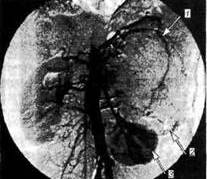

Самолечение недопустимо, следует обращаться к врачу. Доктор выслушает, осмотрит больного, измерит кровяное давление. С целью подтверждения или исключения диагноза врач назначит обычный лабораторный анализ. Специальные исследования выполняются в условиях стационара. Суточная моча пациента исследуется на содержание адреналина, норадреналина и допамина. Для оценки состояния органов ретроперитонального пространства проводят ультразвуковое исследование и компьютерную томографию. Иногда делают рентгенограмму брюшного отдела аорты. В некоторых случаях берут кровь на анализ из вены нижней конечности. Часто кровь пациента содержит избыточное количество лейкоцитов и глюкозы.